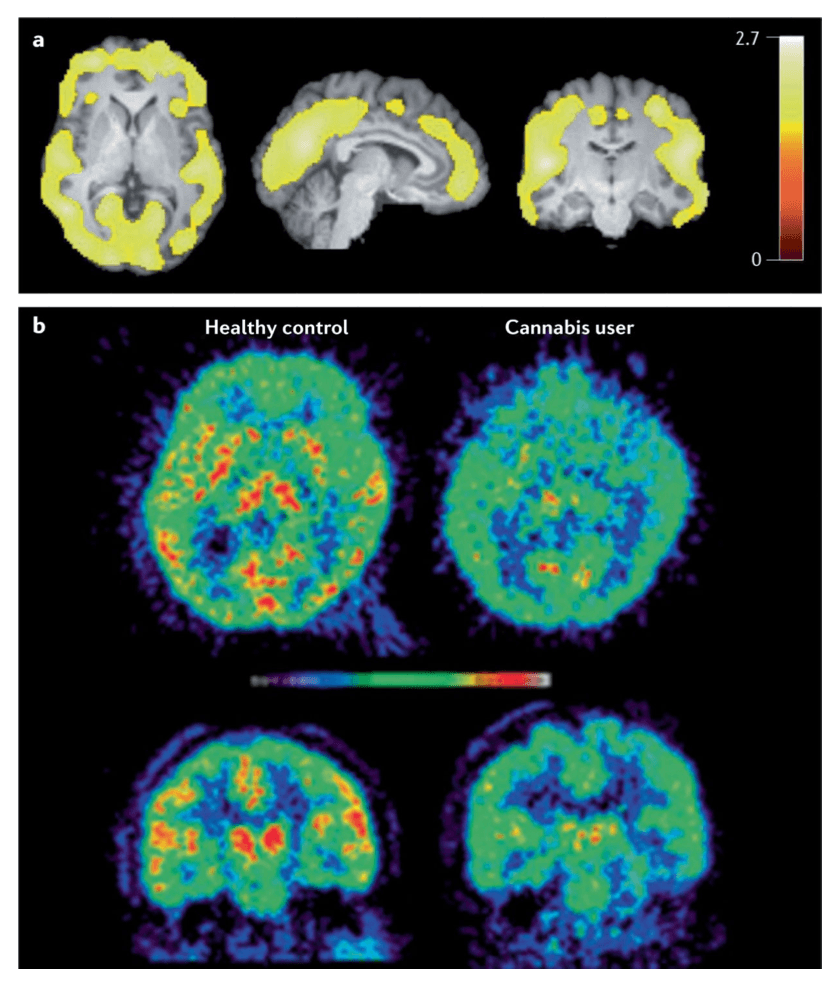

Brain alterations

Chronic administration of THC or CB1 receptor agonists decreases CB1 receptor availability in the limbic system and neocortex in animal and human post-mortem studies (FIG. 2). CB1 receptors are downregulated in individuals with CUD and, in some studies, an inverse association has been found between CB1 receptor density in cortical areas and the duration of cannabis smoking. Other studies have reported that CB1 density normalizes a few days to 4 weeks after cannabis withdrawal, suggesting that the effects of chronic cannabis use on CB1 receptors may be reversible. In addition to downregulation on CB1 receptor density, the endogenous cannabinoid anandamide is downregulated in striatal areas after repeated administration of THC in rodents. Lower levels of anandamide have also been found in the cerebrospinal fluid of people who use cannabis, although the activity of FAAH is lower in the brain of people who use cannabis (FIG. 4). The full effects of chronic cannabis exposure in the cannabinoid system have not yet been elucidated.

Most PET imaging studies of the dopaminergic system in the brains of cannabis users have not identified one of the most consistent changes in other types of drug dependence, namely, a lower availability of striatal D2 and D3 receptors. In addition, chronic THC administration does not affect D2 and D3 receptor availability in nonhuman primates. Chronic cannabis users may have lower capacity to synthesize dopamine as some studies have found lower dopamine release, notably in striatal areas and the globus pallidus, in response to an amphetamine challenge in chronic cannabis users. This may not be the case in individuals with mild to moderate cannabis dependence. In addition, cannabis users have lower dopamine transporter availability than controls in the dorsal striatum, ventral striatum, midbrain, middle cingulate and thalamus. Whether these changes reflect vulnerability factors or neuro-adaptations to cannabis exposure is unclear. Very few other neurobiological systems have been investigated so this area requires more exploration.